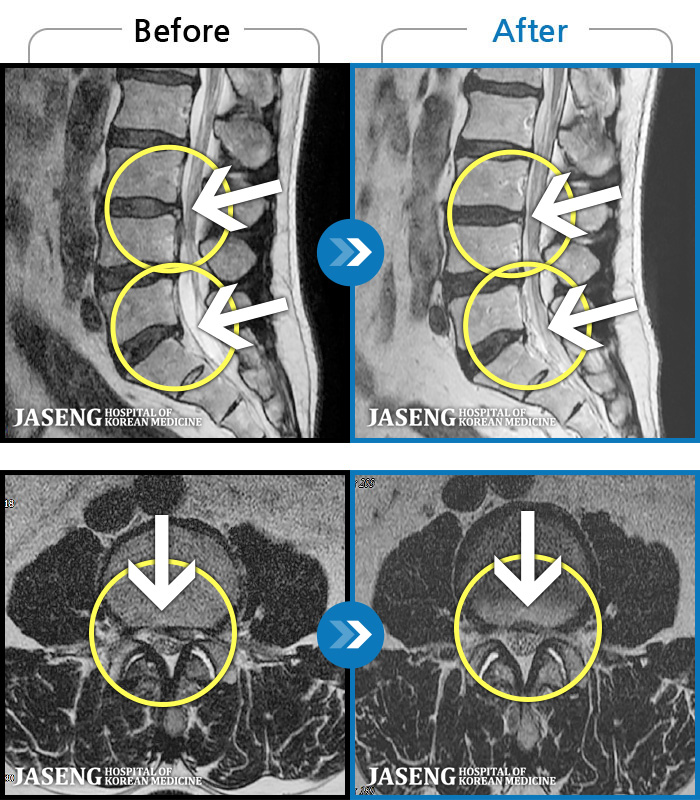

MRI ġ

56 MRI ũ ʸ Ȯϼ.